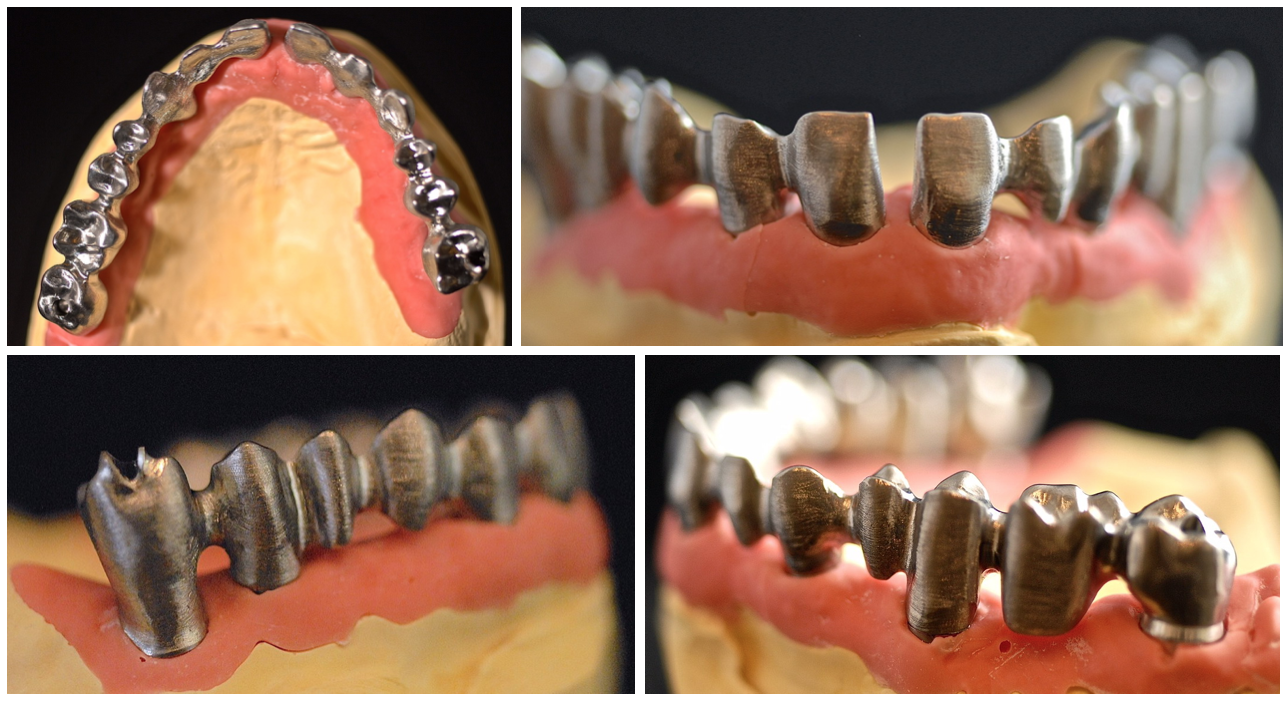

Bridge provisoire transvissé réalisé au laboratoire :

Ce bridge a été réalisé en technique d’impression numérique avec création de la fausse gencive par maquillage de surface

Bridge provisoire en place avec un rendu esthétique satisfaisant :

Détail de la fausse gencive du bridge provisoire en bouche :